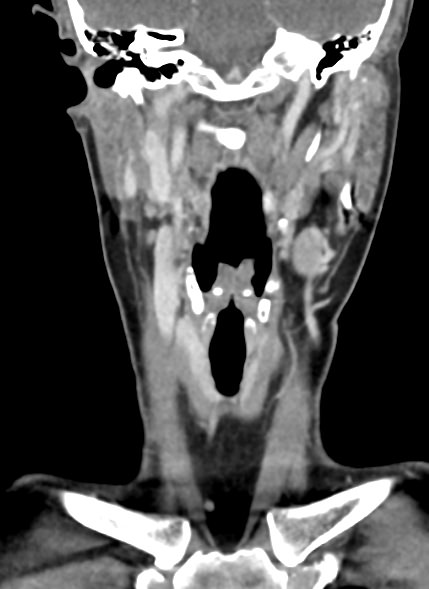

Оптимальным методом обследования гортани и голосовых связок является мультиспиральная компьютерная томография. Метод позволяет подробно визуализировать состояние данной анатомической области и выявить патологические изменения, которые незаметны при ларингоскопии (визуальный осмотр гортани с помощью специальных инструментов), проведении УЗИ и обычной рентгенографии.

Компьютерная томография позволяет оценить состояние костного скелета гортани и особенно важна в оценке состояния хрящей гортани, которые лучше всего визуализируются с помощью данного исследования. В частности, мультиспиральная КТ позволяет выявить распространение рака гортани в ткань щитовидного хряща и другие окружающие структуры.

При подозрении на опухоль гортани нативная мультиспиральная КТ дополняется проведением внутривенного болюсного контрастирования. Для этого пациенту внутривенно вводится контрастный препарат на основе йода.

Контраст хорошо накапливается в патологически измененных участках, за счет этого становятся отчетливо видны на снимках их границы, размеры, точная локализация относительно окружающих здоровых тканей. По характеру накопления контраста можно отличить доброкачественные опухоли от злокачественных, определить степень распространенности процесса, выявить поражение регионарных лимфатических узлов.

На полученных снимках можно оценить состояние всех структурных элементов гортани, голосовых складок, хрящей, а также лимфатических узлов, сосудов и шейных позвонков на исследуемом уровне. Инновационные возможности аппаратов позволяют построить 3D-модель зоны исследования, которая дает наглядную картину пространственного расположения органов, что бывает особенно важно при планировании хирургических операций.